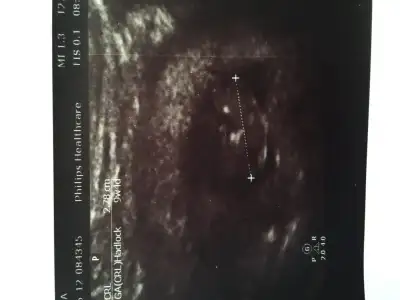

Kızlarrrrr çıktım doktorun yanından akıntıyı söyledim kokulu değilse aşırı değilse sorun yok normal şuan ilaç için çok erken dedi.....bu arada bebişim erkekmişşşşş idrar sonucunu bekliyorumm

Saol cnm cinsiyet soylimmi dedi eveeeeettttttt dedin erkek dediAaa kesin mi dedi?Hayırlı olsun canımm

Hayırlı olsun oğluşun canımKızlarrrrr çıktım doktorun yanından akıntıyı söyledim kokulu değilse aşırı değilse sorun yok normal şuan ilaç için çok erken dedi.....bu arada bebişim erkekmişşşşş idrar sonucunu bekliyorumm

Saol cnm cinsiyet soylimmi dedi eveeeeettttttt dedin erkek dediemin konuştu

Hayırlı olsun canımKızlarrrrr çıktım doktorun yanından akıntıyı söyledim kokulu değilse aşırı değilse sorun yok normal şuan ilaç için çok erken dedi.....bu arada bebişim erkekmişşşşş idrar sonucunu bekliyorumm